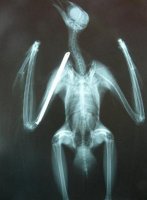

Peñalara presentaba fractura abierta de húmero por disparo.

Susana, fisioterapeuta de GREFA e Iván, voluntario del Area de Rehabilitación explicaron detalladamente a los numerosos socios presentes en la conmemoración algunos aspectos de la biología, hábitat y cosumbres de esta especie, así como la atención que recibió desde que ingresó, gravemente herida y recibió la atención de urgencia del equipo de veterinarios,que lograron estabilizarla e intervenirla quirúrgicamente, hasta su posterior recuperación mediante fisioterapia y técnicas de musculación.